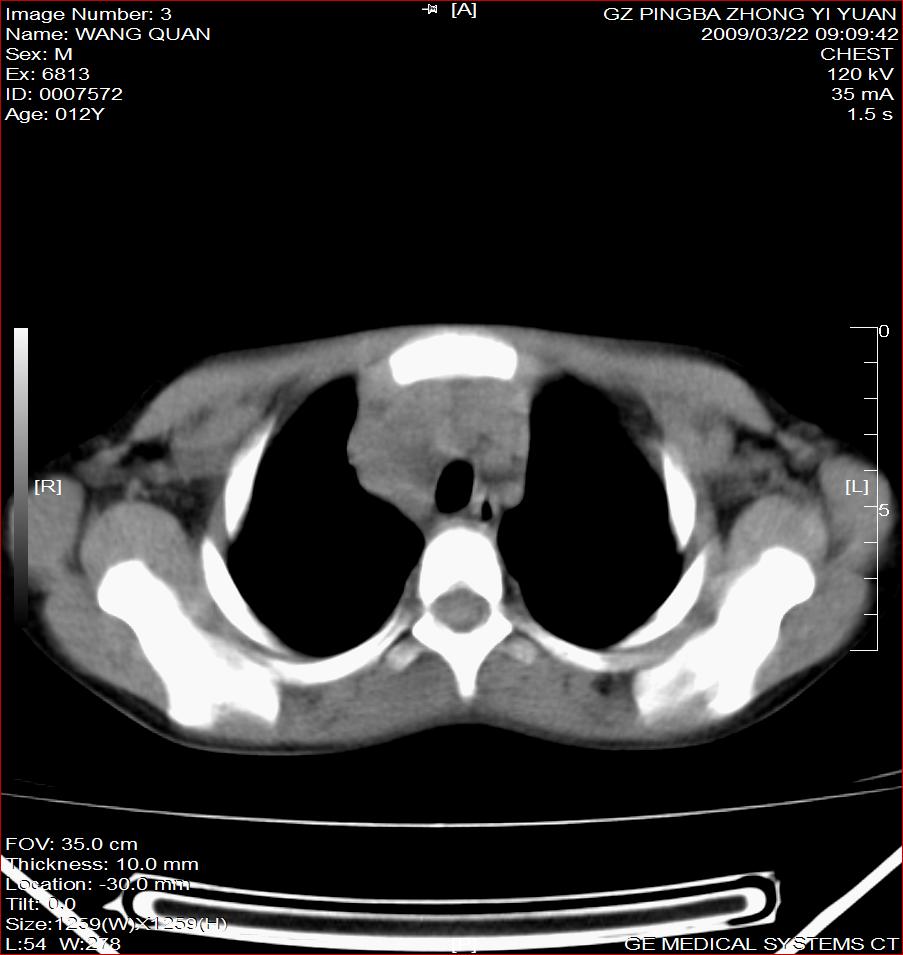

以下是引用随光逐影在2009-3-23 8:12:00的发言:[br]1)右肺门及纵隔淋巴结结核。2)两肺急性血行播散型肺结核可能。3)右侧支气管内膜结核?建议必要时行纤支镜检查。4)右侧少量胸腔积液。